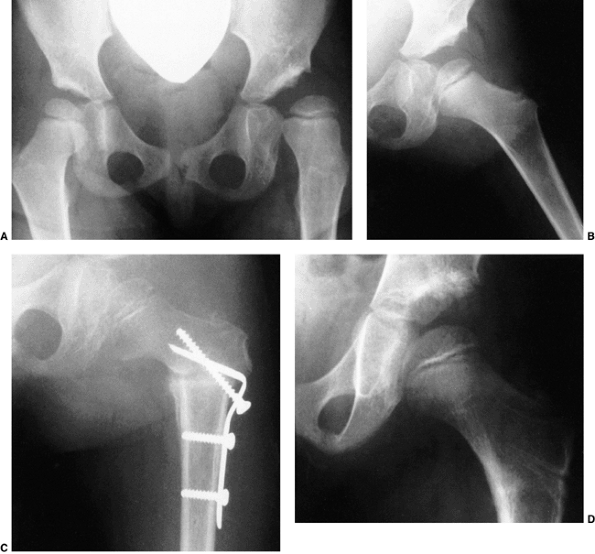

![]() |

Figure 24.20

A 65-year-old woman with bilateral, untreated developmental dislocations of the hips complained of some low back pain, but had no hip pain. She had a waddling gait and hyperlordosis. |

|

Figure 24.21

Radiograph of a 43-year-old woman with complete dislocation of both hips. She is asymptomatic on the right side but has disabling symptoms from the left hip. She has no false acetabulum on the right, but has a well-developed false acetabulum on the left with secondary degenerative changes. [From Weinstein SL. Natural history of congenital hip dislocation (CDH) and hip dysplasia. Clin Orthop 1987;225:62, with permission.] |

Figure 24.22

A 45-year-old woman with bilateral complete dislocations, hip flexion deformity, and marked hyperlordosis. The patient’s only reported symptoms concerned her back. |